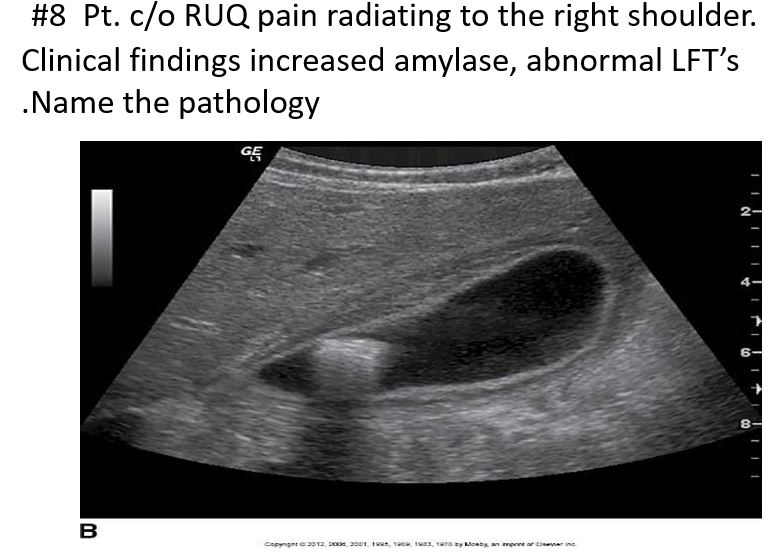

increased Serum amylase / alkaline phosphatase

Abnormal LFTs

Acute Cholecystitis

≥ Serum amylase

Abnormal LFTs

Pathology: Choledocholithiasis